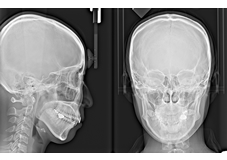

セファロ画像

従来のレントゲンでは、平面での診断しかできませんでしたがCTでは3次元的に立体画像で確認ができる為、骨の厚みや神経までの距離、血管の位置など正確に把握することができます。